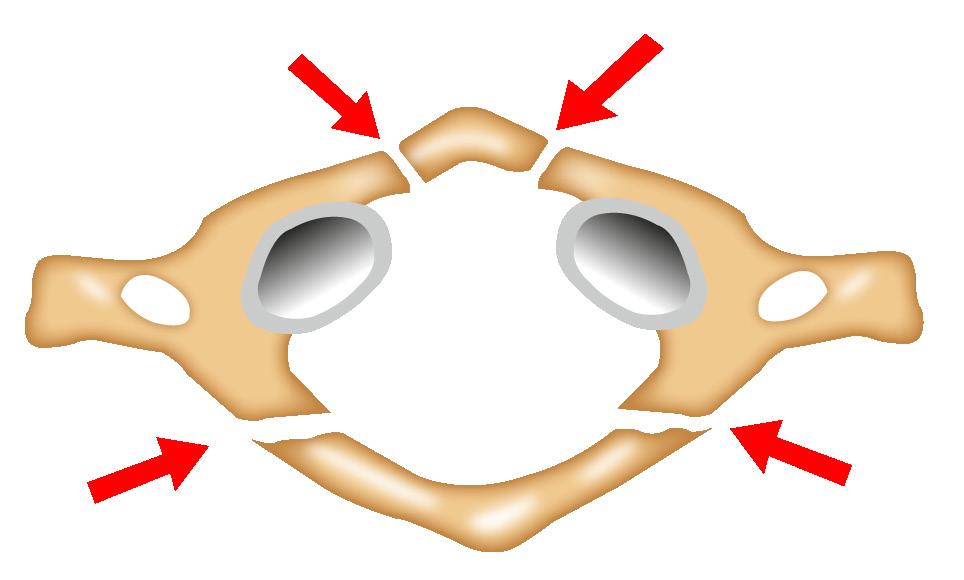

Fractura del atlas (vértebra c1)

La fractura en estallido es también llamada fractura de Jefferson, es una fractura muy inestable.

Su mecanismo es debido a fuerzas de compresión vertical a través de los cóndilos occipitales a las masas laterales del atlas, empujando a estas masas lateralmente, llevando a fracturas de los arcos anterior y posterior de la vertebra C1 con o sin rotura del ligamento transverso, si está presenta determina la inestabilidad.(Ver Figura 47)

En la radiografía se aprecia un aumento entre el C1 y el odontoides (en vista lateral), en la vista anteroposterior se apreciará un desplazamiento de las masas laterales de la vértebra C1 lateralmente a los márgenes exteriores de los pilares articulares de C2. (Ver Figura 48)